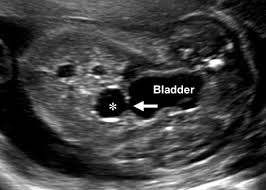

Adnexal Masses In Pregnancy from www.perinatology.com

Ovarian cysts are often identified when an ultrasound examination is performed for another reason.